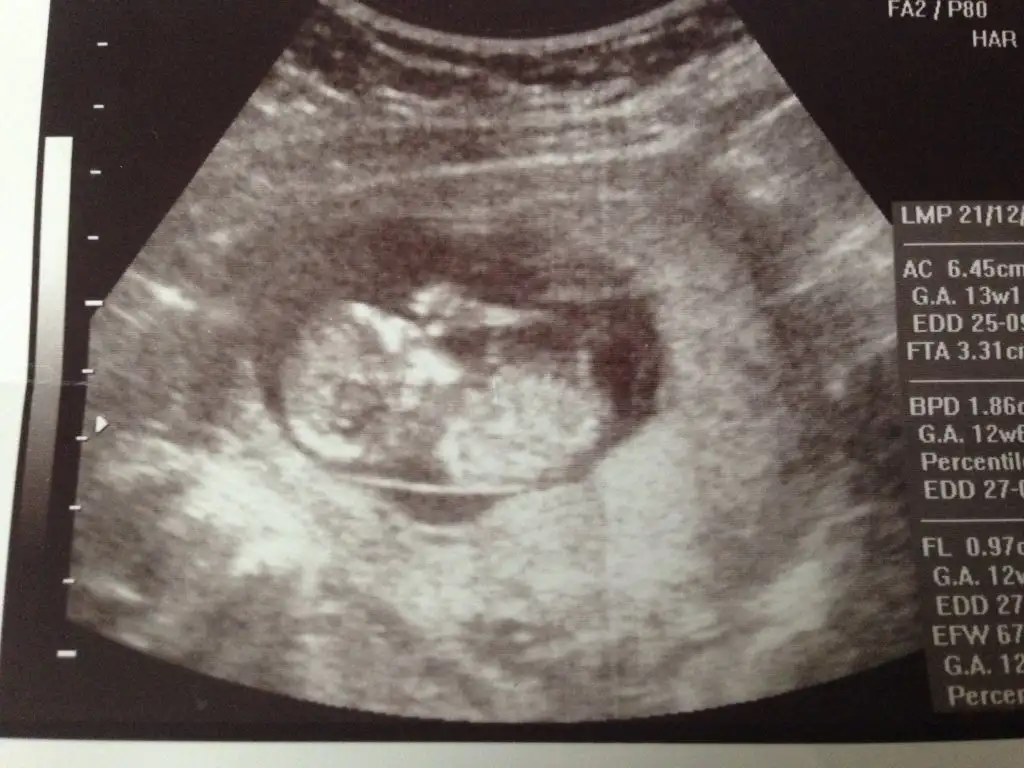

dr soylemeden siz gorun genital nub teorisi ( bebegin cinsiyeti)

Benim minik ordegime de tahmin yapar misiniz ablalari?

Erkek